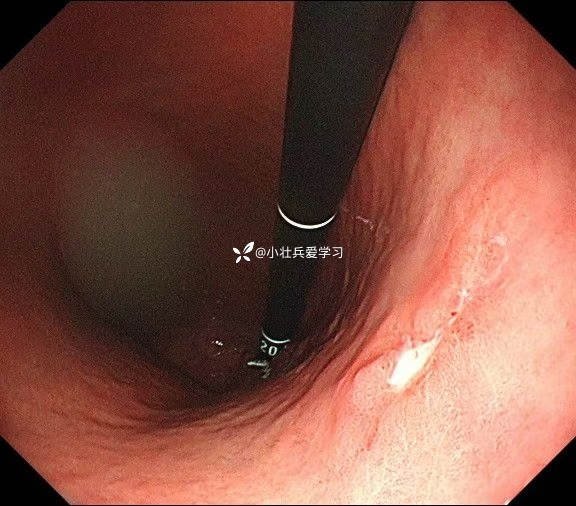

临床诊断:溃疡型胃角早癌

术前谈话诊断性ESD

术后病理示粘膜内癌(M3期),切缘阴性,达到治愈性切除标准,术后不用再追加外科手术、放化疗,对病人来说是不幸中的万幸。